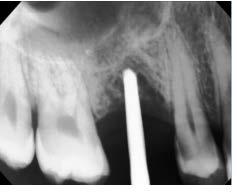

Figura 2. Radiografías periapicales de órganos dentarios con posibilidad de mantenerse en boca.

hace 8 años por lo que toma 30 mg de nifedipino cada 12 horas, amlodipino 5 mg cada 24 horas, telmisartan 40 mg cada 12 horas y metropolol 100 mg cada 12 horas, además comenta padecer diabetes mellitus tipo II desde hace 7 años por lo que también toma 50 mg de metformina cada 12 horas y dapagliflozina 10 mg cada 24 horas. Clínicamente se observó una encía roja y sangrante, profundos sondeos, una notable hiperplasia gingival, depósitos de cálculo y movilidad dental grado III en todos los órganos dentarios a excepción del segundo premolar superior derecho al canino superior izquierdo, quienes presentaban una movilidad grado II. Radiográficamente se encontró una pérdida de inserción radiográfica avanzada generalizada

en la arcada inferior, y grupos molares de ambos cuadrantes superiores (Figura 1), los únicos órganos dentarios con posibilidad de preservación en boca a través de terapia periodontal se encontraron en el sector anterior de la arcada superior anteriormente mencionados con movilidad grado II